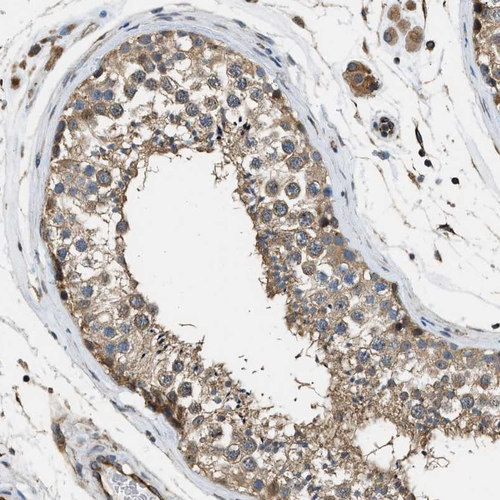

Immunohistochemical staining of human cerebellum shows strong cytoplasmic positivity in Purkinje cells.